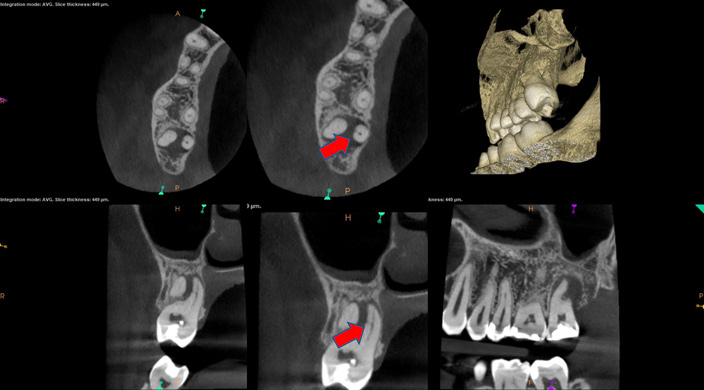

In the first case study, a young female patient was told she had a tooth (tooth No. 2, Figure 3) that should be extracted due to extensive bone loss. Using CBCT, the clinician was able to identify a large lateral canal within the palatal root. Despite the bone loss, the patient was eager to save her tooth. He offered to treat the tooth with the broad-spectrum acoustic technology. As shown in Figure 4, the preparation space was much smaller, which he was able to obturate efficiently. In addition, the small pinpoint of sealer in the middle of the palatal root indicated that the palatal lateral canal had been addressed (Figure 5). In the clinician's opinion, this area was likely the primary source of much of the bone loss.

Figure 6 through Figure 8 demonstrate that, 5 months after the procedure, complete healing had occurred, notably on the distal, where the probing had resolved to 2 mm. The patient then had a crown placed by her general dentist. Given her positive experience with the technology, she was eager to return as needed for continued follow-up.

Fig 3. Case 1: CBCT showed a large lateral canal within the palatal root (Fig 3). There was a small preparation space, which was efficiently obturated (Fig 4). A small pinpoint of sealer in the middle of the palatal root indicated that the palatal lateral canal had been addressed (Fig 5). After 5 months, CBCT demonstrated complete healing (Fig 6), notably on the distal, where probing had resolved to 2 mm. Radiographic images were taken immediately postoperatively (Fig 7) and 5 months postoperatively (Fig 8).

Fig 4. Case 1: CBCT showed a large lateral canal within the palatal root (Fig 3). There was a small preparation space, which was efficiently obturated (Fig 4). A small pinpoint of sealer in the middle of the palatal root indicated that the palatal lateral canal had been addressed (Fig 5). After 5 months, CBCT demonstrated complete healing (Fig 6), notably on the distal, where probing had resolved to 2 mm. Radiographic images were taken immediately postoperatively (Fig 7) and 5 months postoperatively (Fig 8).

Fig 5. Case 1: CBCT showed a large lateral canal within the palatal root (Fig 3). There was a small preparation space, which was efficiently obturated (Fig 4). A small pinpoint of sealer in the middle of the palatal root indicated that the palatal lateral canal had been addressed (Fig 5). After 5 months, CBCT demonstrated complete healing (Fig 6), notably on the distal, where probing had resolved to 2 mm. Radiographic images were taken immediately postoperatively (Fig 7) and 5 months postoperatively (Fig 8).

Fig 6. Case 1: CBCT showed a large lateral canal within the palatal root (Fig 3). There was a small preparation space, which was efficiently obturated (Fig 4). A small pinpoint of sealer in the middle of the palatal root indicated that the palatal lateral canal had been addressed (Fig 5). After 5 months, CBCT demonstrated complete healing (Fig 6), notably on the distal, where probing had resolved to 2 mm. Radiographic images were taken immediately postoperatively (Fig 7) and 5 months postoperatively (Fig 8).

Fig 7. Case 1: CBCT showed a large lateral canal within the palatal root (Fig 3). There was a small preparation space, which was efficiently obturated (Fig 4). A small pinpoint of sealer in the middle of the palatal root indicated that the palatal lateral canal had been addressed (Fig 5). After 5 months, CBCT demonstrated complete healing (Fig 6), notably on the distal, where probing had resolved to 2 mm. Radiographic images were taken immediately postoperatively (Fig 7) and 5 months postoperatively (Fig 8).

Fig 8. Case 1: CBCT showed a large lateral canal within the palatal root (Fig 3). There was a small preparation space, which was efficiently obturated (Fig 4). A small pinpoint of sealer in the middle of the palatal root indicated that the palatal lateral canal had been addressed (Fig 5). After 5 months, CBCT demonstrated complete healing (Fig 6), notably on the distal, where probing had resolved to 2 mm. Radiographic images were taken immediately postoperatively (Fig 7) and 5 months postoperatively (Fig 8).